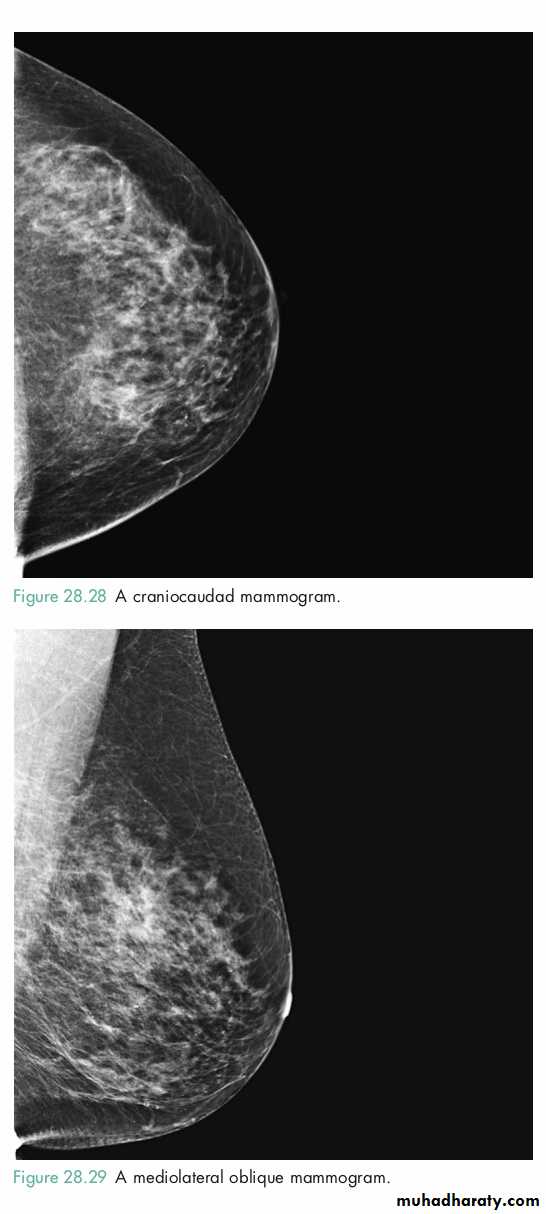

MammographySoft tissue X-rays are taken by placing the breast in direct contact with ultrasensitive film and exposing it to low-voltage, high-amperage X-rays.

The dose of radiation is approximately 0.1 Gy and therefore mammography is a very safe investigation.